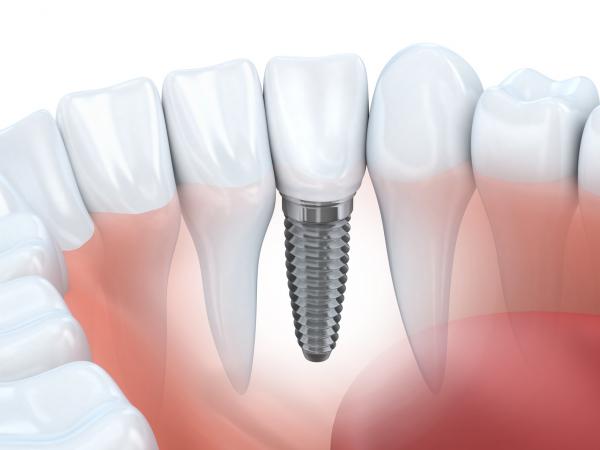

11インプラント

IMPLANT

インプラント治療とは永久歯を失った箇所に金属製の歯根を埋め込み、その上に人工の歯を装着する治療法です。インプラントは審美性に優れており、咀嚼力が高く、ブリッジや入れ歯に比べ、他の歯に負担をかけずに歯を再建することができる治療法です。